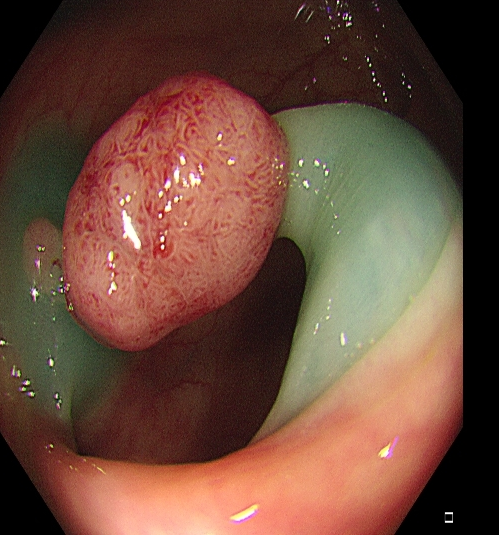

适用于不同大小隆起型病变Ⅰp型、Ⅰsp 型以及小型(<2 cm)Ⅰs型(具体分型标准可参照内镜发现消化道早癌,分型太多不知道怎么判断?这篇文章讲清楚了)病变的切除。小型Ⅰp型病变,圈套切除相对简单,可采用冷或热圈套切除,切除时应在保证完整切除病变同时,保留一定长度的蒂部或与肠壁保持一定距离,收紧圈套后,应抖动圈套器,观察有无周围正常肠黏膜一并套入,防止损伤肠壁。

图2 小型Ⅰsp 型病变热圈套切除示意图

对于大型Ⅰp病变,除以上注意事项外,应采用热圈套方式切除,切除前应于蒂根部充分黏膜下注射(经内镜注射针将2~10 mLl万单位的肾上腺素+亚甲蓝+生理盐水混合液注射于黏膜下,边退针边注射),致使蒂部充分隆起,易于切除(图 3),切除过程中病变应避免接触肠壁,以免形成闭合回路,灼伤肠壁。